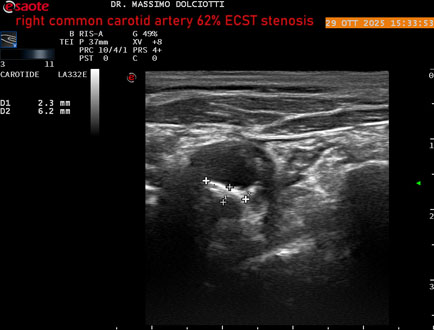

Data inserimento: 30/10/2025

Ecografia del: 29/10/2025

Strumento: Esaote MyLab Eight

Sonda: Lineare Multifrequenza 3-11 MHz

Età Paziente: F 75 anni

Motivazione dell'esame: controllo in pz con ateromasia carotidea ed ipercolesterolemia.

Commento all'esame: le immagini ed il video documentano all'arteria carotide comune destra placca disomogenea tipo 3 della classificazione di Gray Weale, che determina stenosi del 62% calcolato con metodo ECST.

Conclusioni: stenosi del 62% ECST dell'arteria carotide comune destra (62% ECST stenosis of the right common carotid artery).

Presentazione: Dr. Massimo Dolciotti - Ancona

Elaborazione digitale: Andrea Dini - Ancona